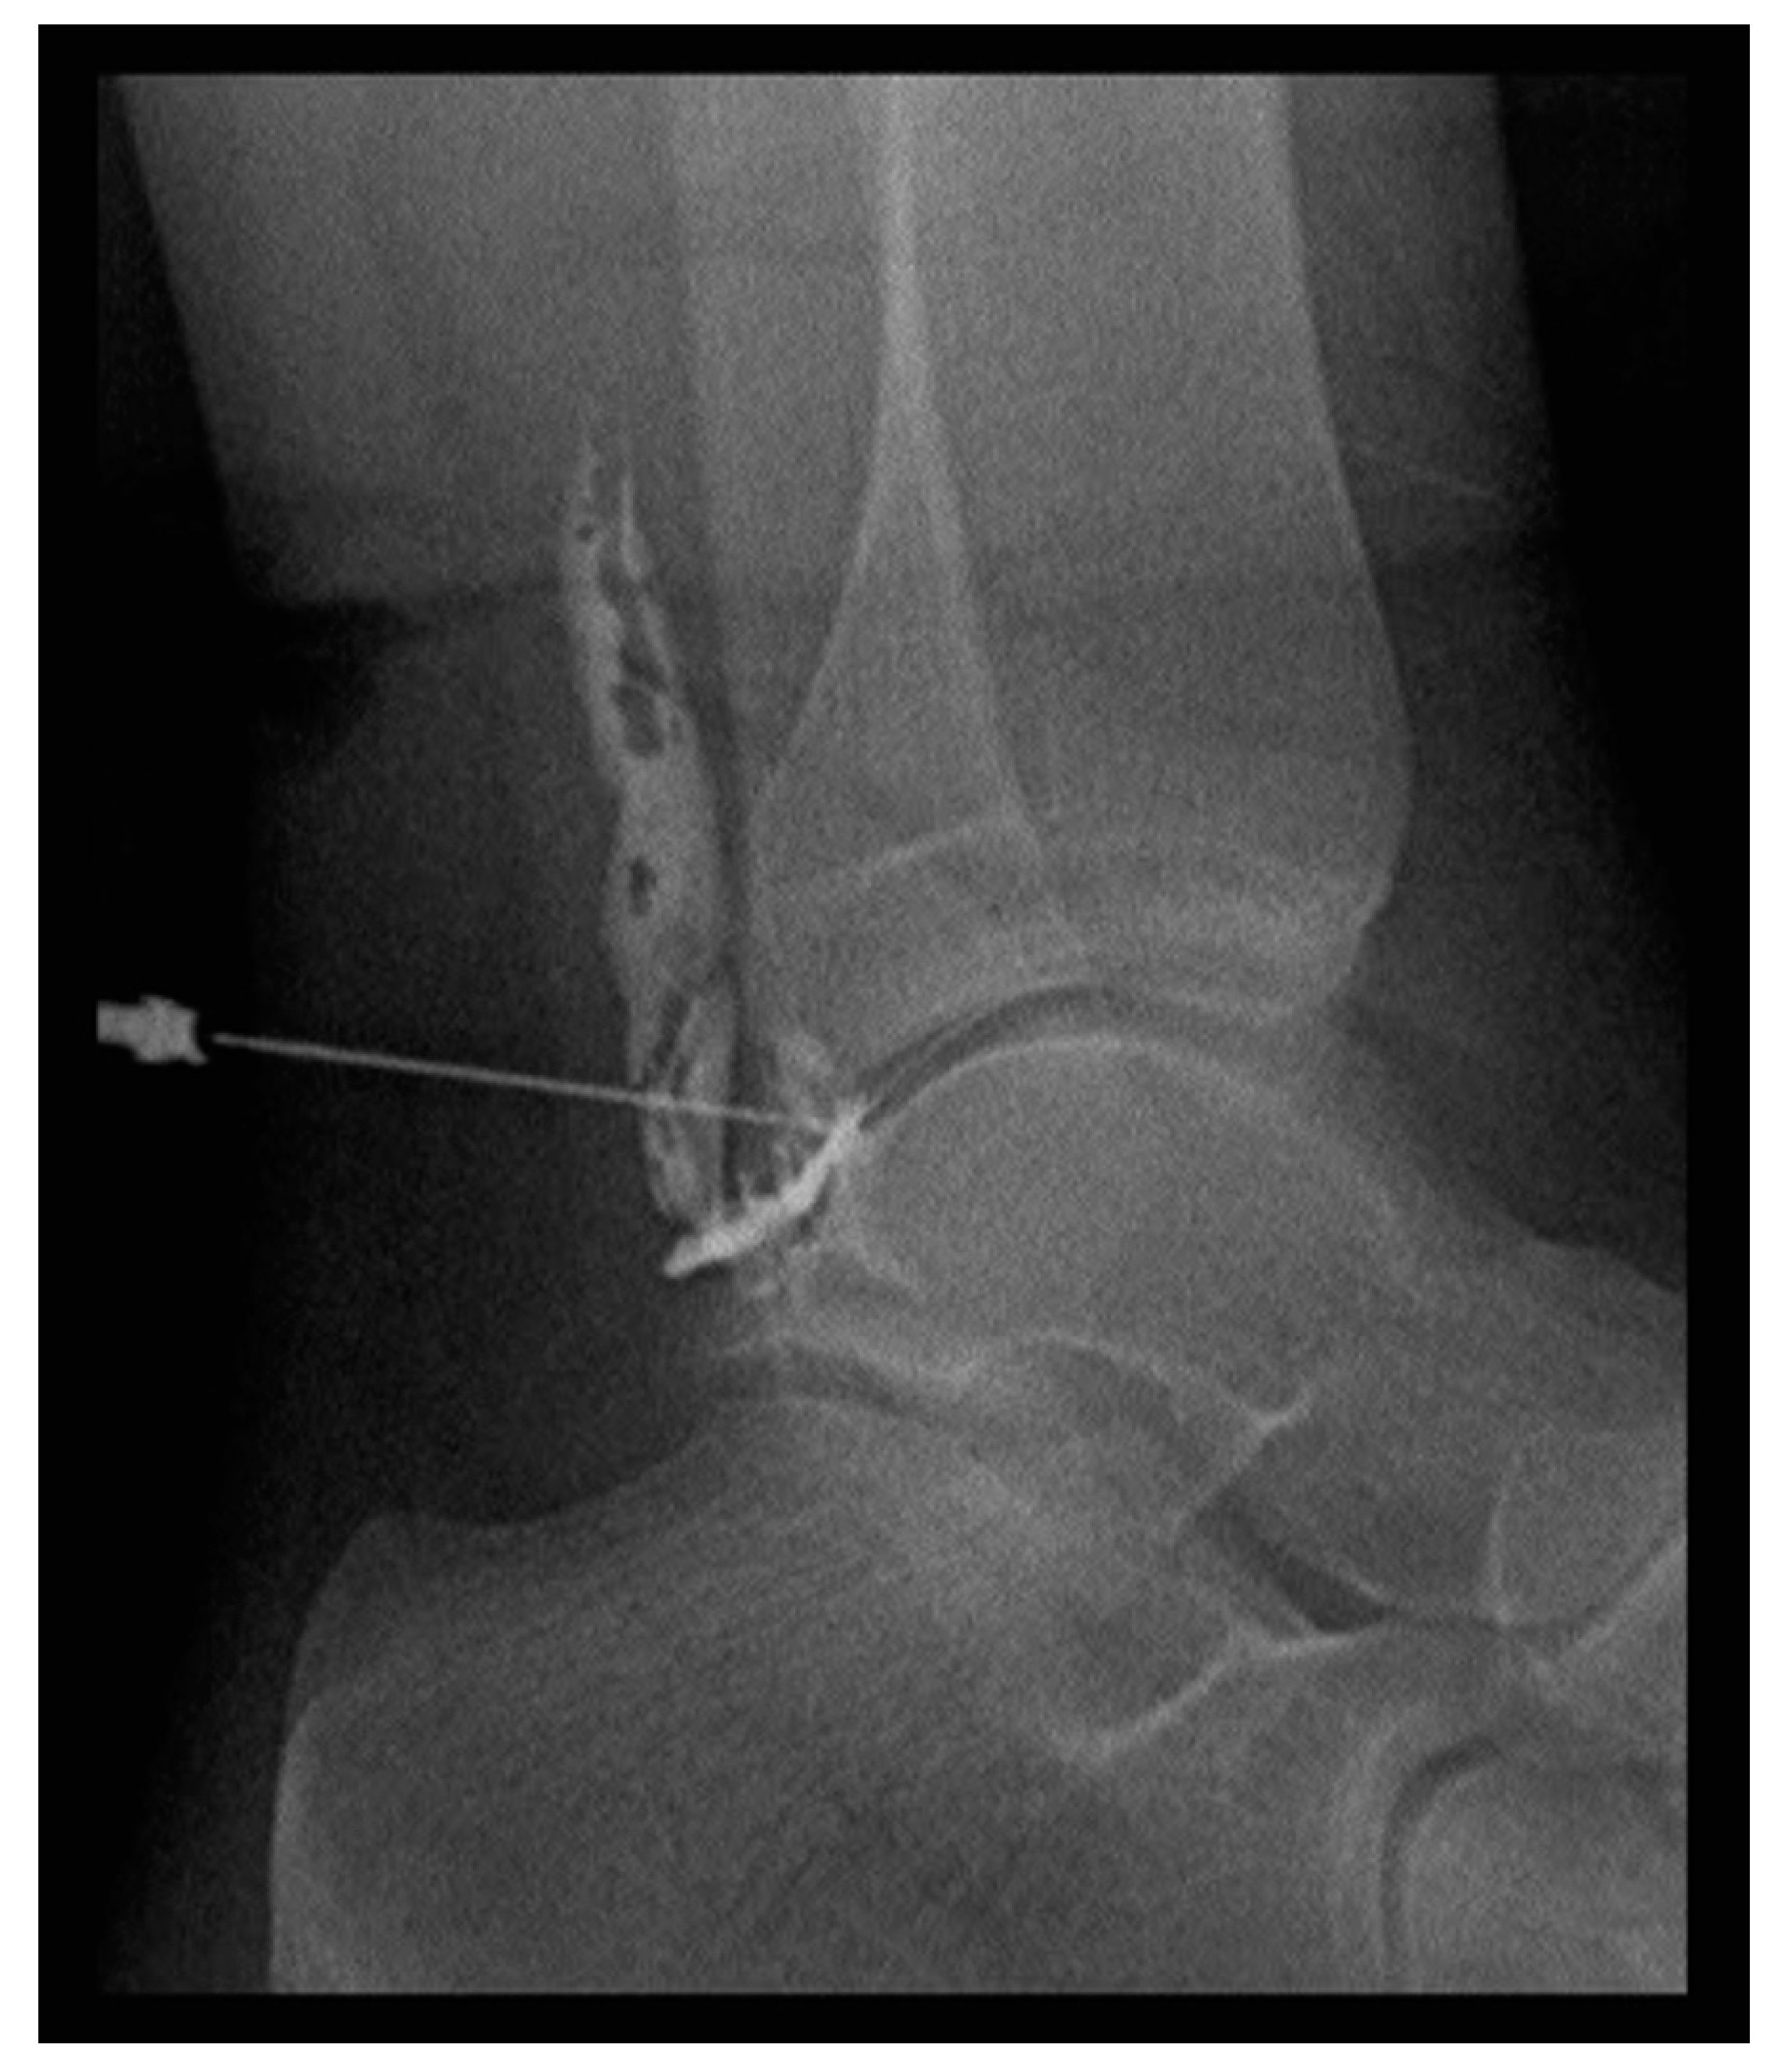

2.3. Radiosynoviorthesis (RSO)